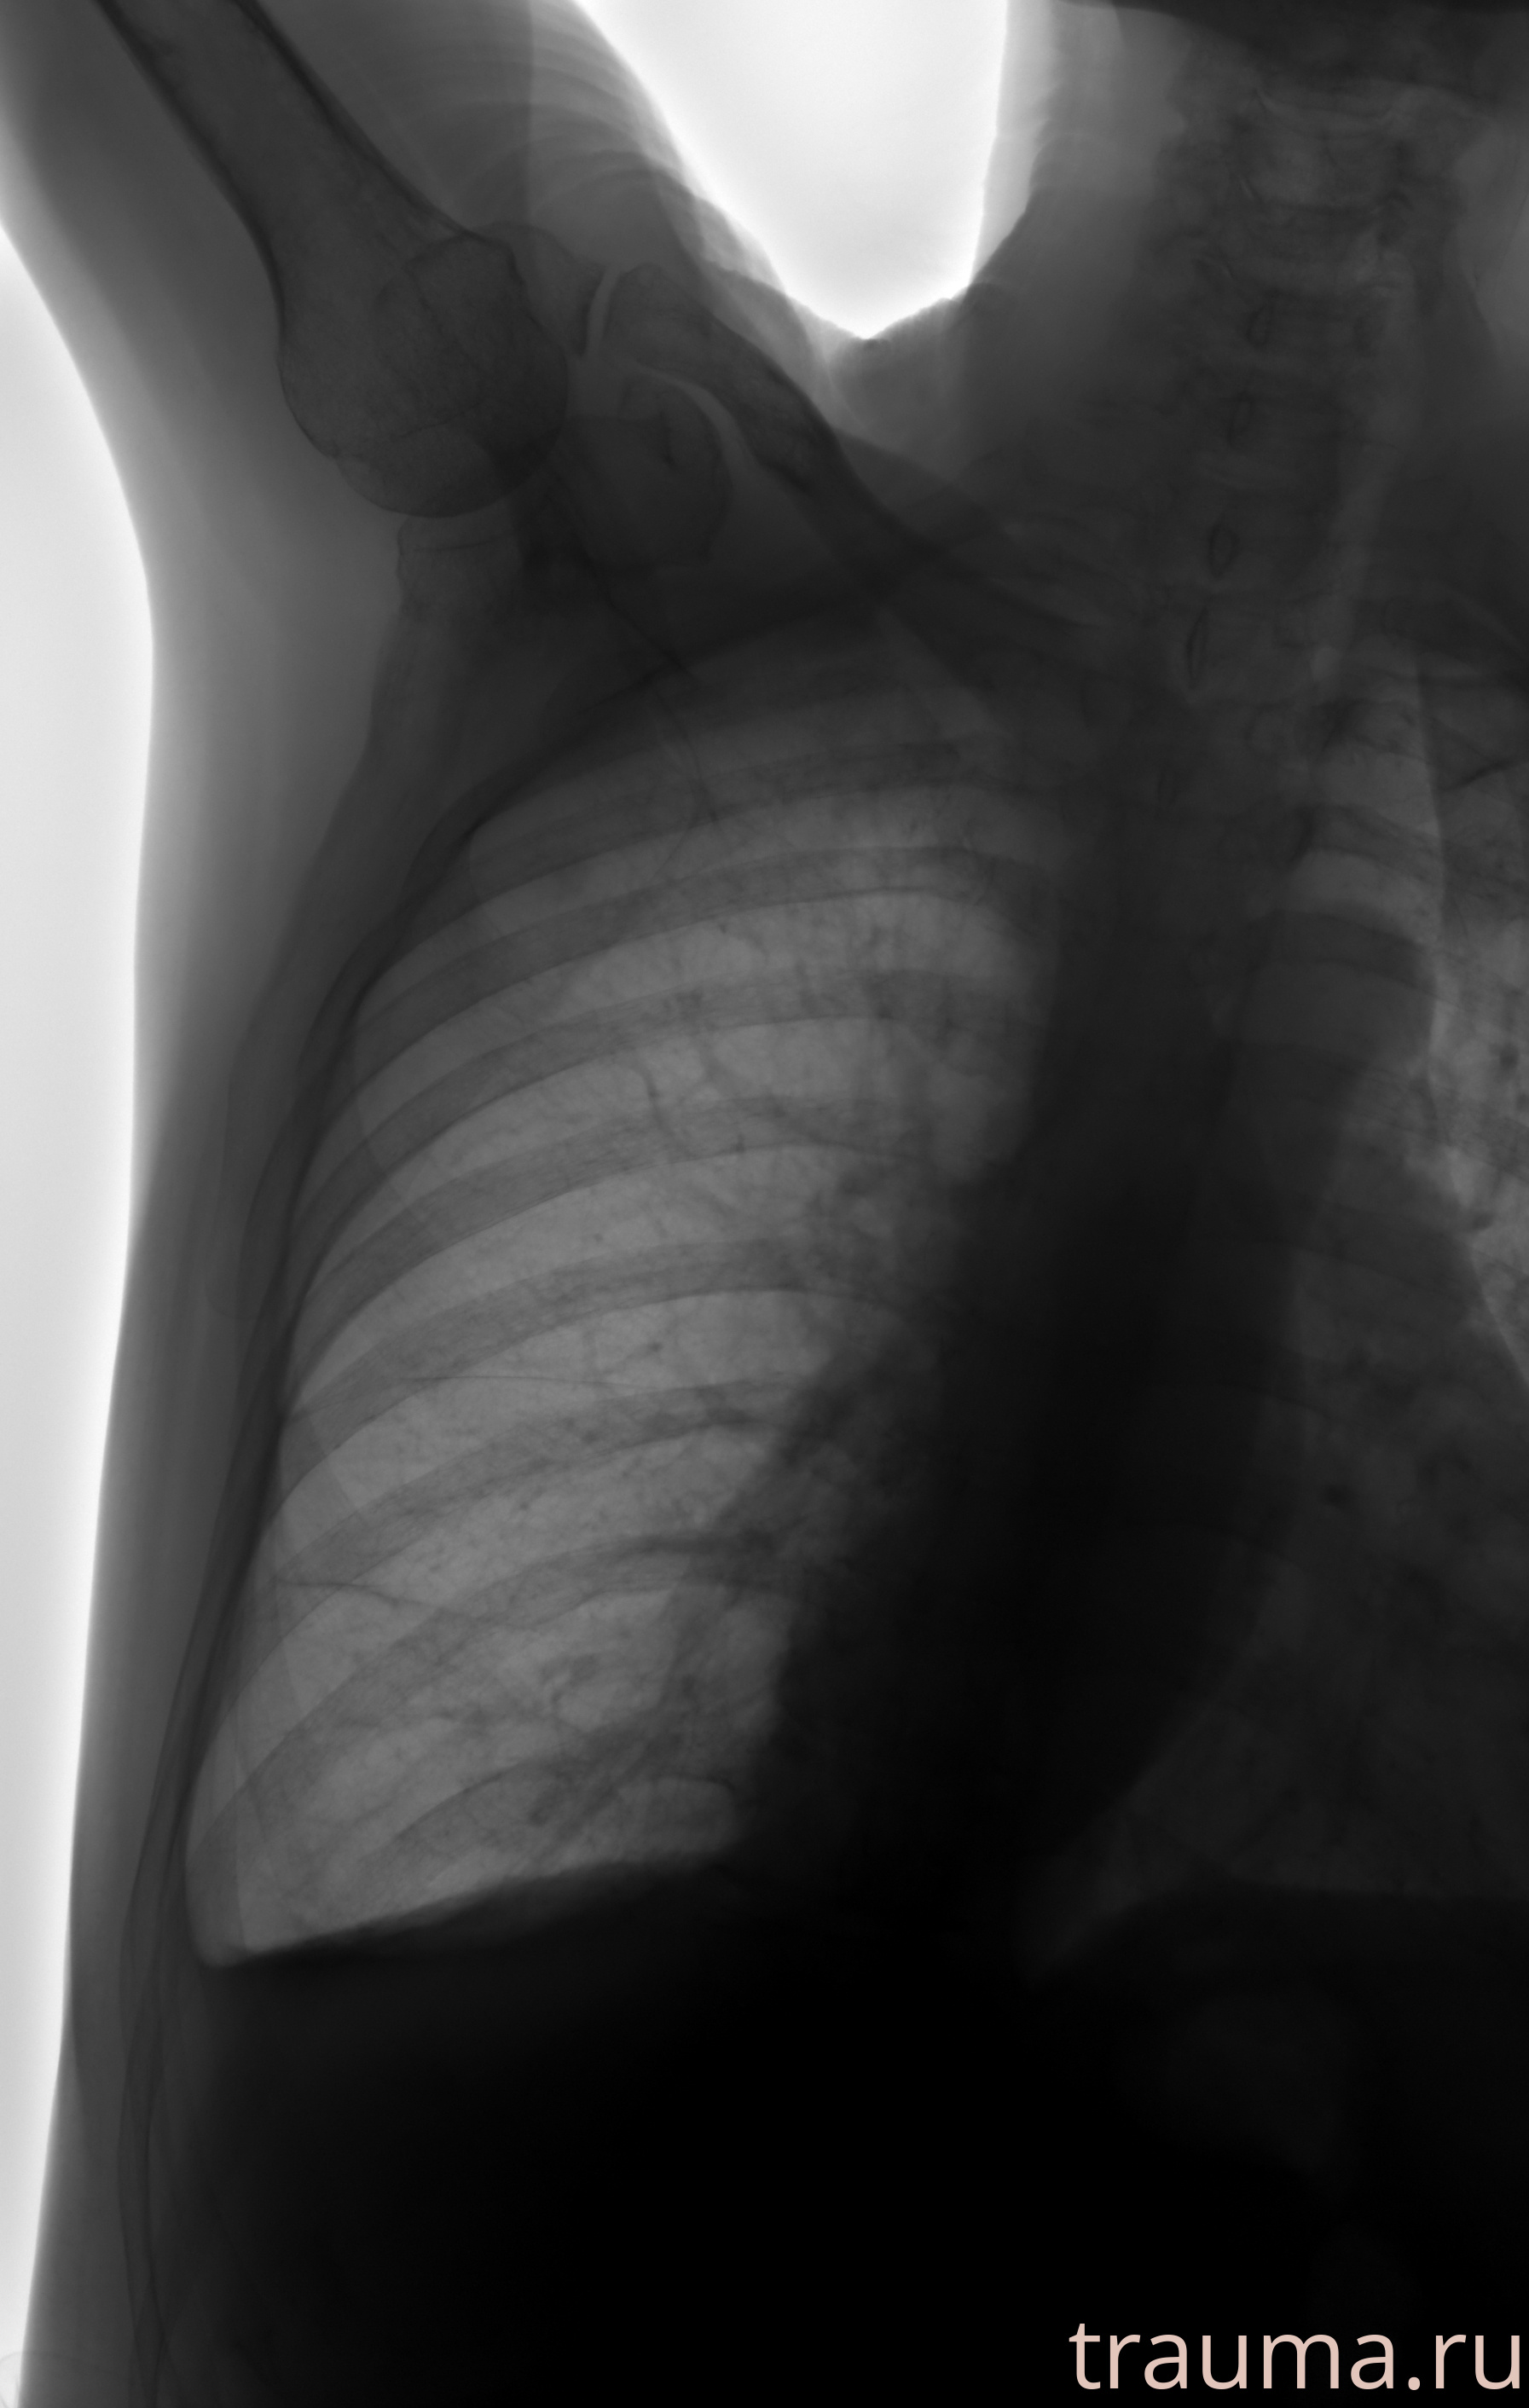

Рентгенограммы

Натуживание 26.12.2025 21:16:34